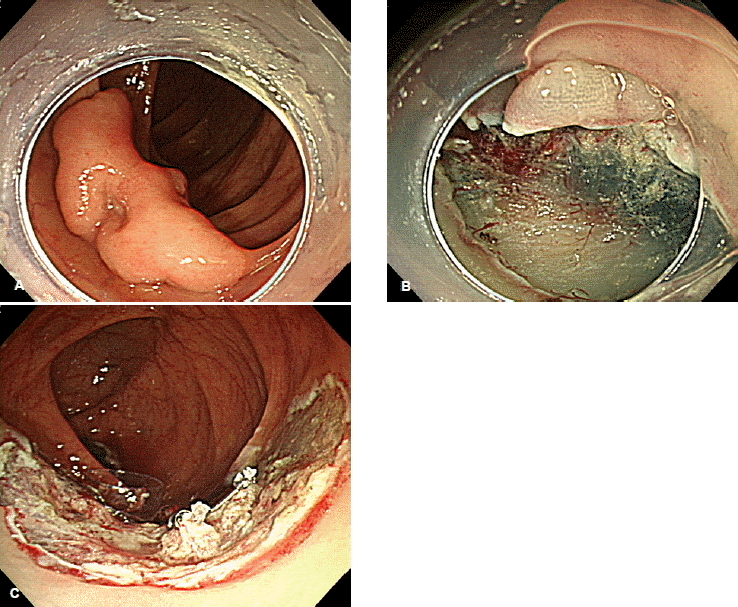

내시경점막하박리술은 점막하 용액 주입 후 절개도를 이용해 점막하층을 박리하여 종양을 절제해 내는 방법이므로 이론적으로는 병변의 크기에 상관 없이 일괄절제가 가능하다. 실제 여러 연구에서도 큰 대장종양에 대한 내시경점막하박리술의 일괄절제율은 80~90% 정도로 높게 보고되고 있다21). 그러나 대장벽은 매우 얇아 내시경점막하박리술을 시행할 경우 5% 전후의 비교적 높은 천공 위험성이 있으며, 점막하박리술을 이용한 일괄절제에 걸리는 시간도 적지 않다는 문제가 있다22-24). 따라서 대장에서의 내시경점막하박리술이 가장 활발히 이루어지고 있는 일본에서는 조기대장암이 의심되면서, 2 cm 이상으로 크고, 올가미를 이용한 전통적인 내시경절제술 기법들로는 일괄절제가 불가능해 보이는 경우에 한해 내시경점막하박리술을 시행하도록 권고하고 있다(그림. 2)25). 최근에는 종양을 박리되는 반대면으로 당겨서 시술을 쉽게 하기 위한 부속기기 개발26,27), sodium hyaluronate 점막하 주입액 도입28), 대장 확장으로 인한 불편감 최소화 위해 CO2 사용29) 등과 같은 새로운 시도들이 지속되면서, 대장 내시경점막하박리술이 과거에 비해 용이해지고 있는 실정이다.

Figure 2.

(A) A non-granular laterally spreading tumor is seen. (B) En bloc resection by snaring appeared to be difficult because of its large size and sessile appearance. Therefore, endoscopic submucosal dissection was performed. (C) En bloc resection was done and the post-resection ulcer showed no remnant lesion.